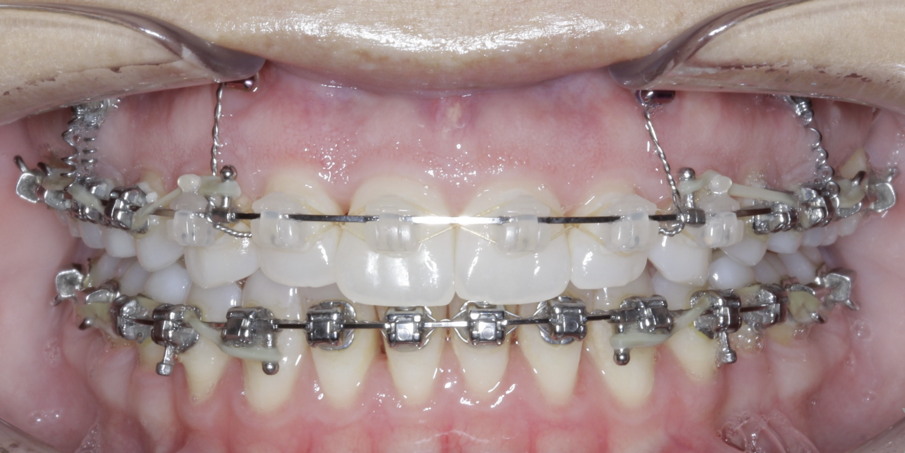

TADs are placed at the second visit with a 14 × 25 mm copper (Cu) and nickel–titanium (NiTi) wire and are tied from the anchor to the wire with an elastic thread (surgical thread; Fig. 6). Once the patient has progressed to larger Cu–NiTi wires and stainless steel, the TADs are tied to the wire using a power chain looped to the wire, or NiTi closing springs, depending on the thickness of the tissue (Figs. 7 & 8).